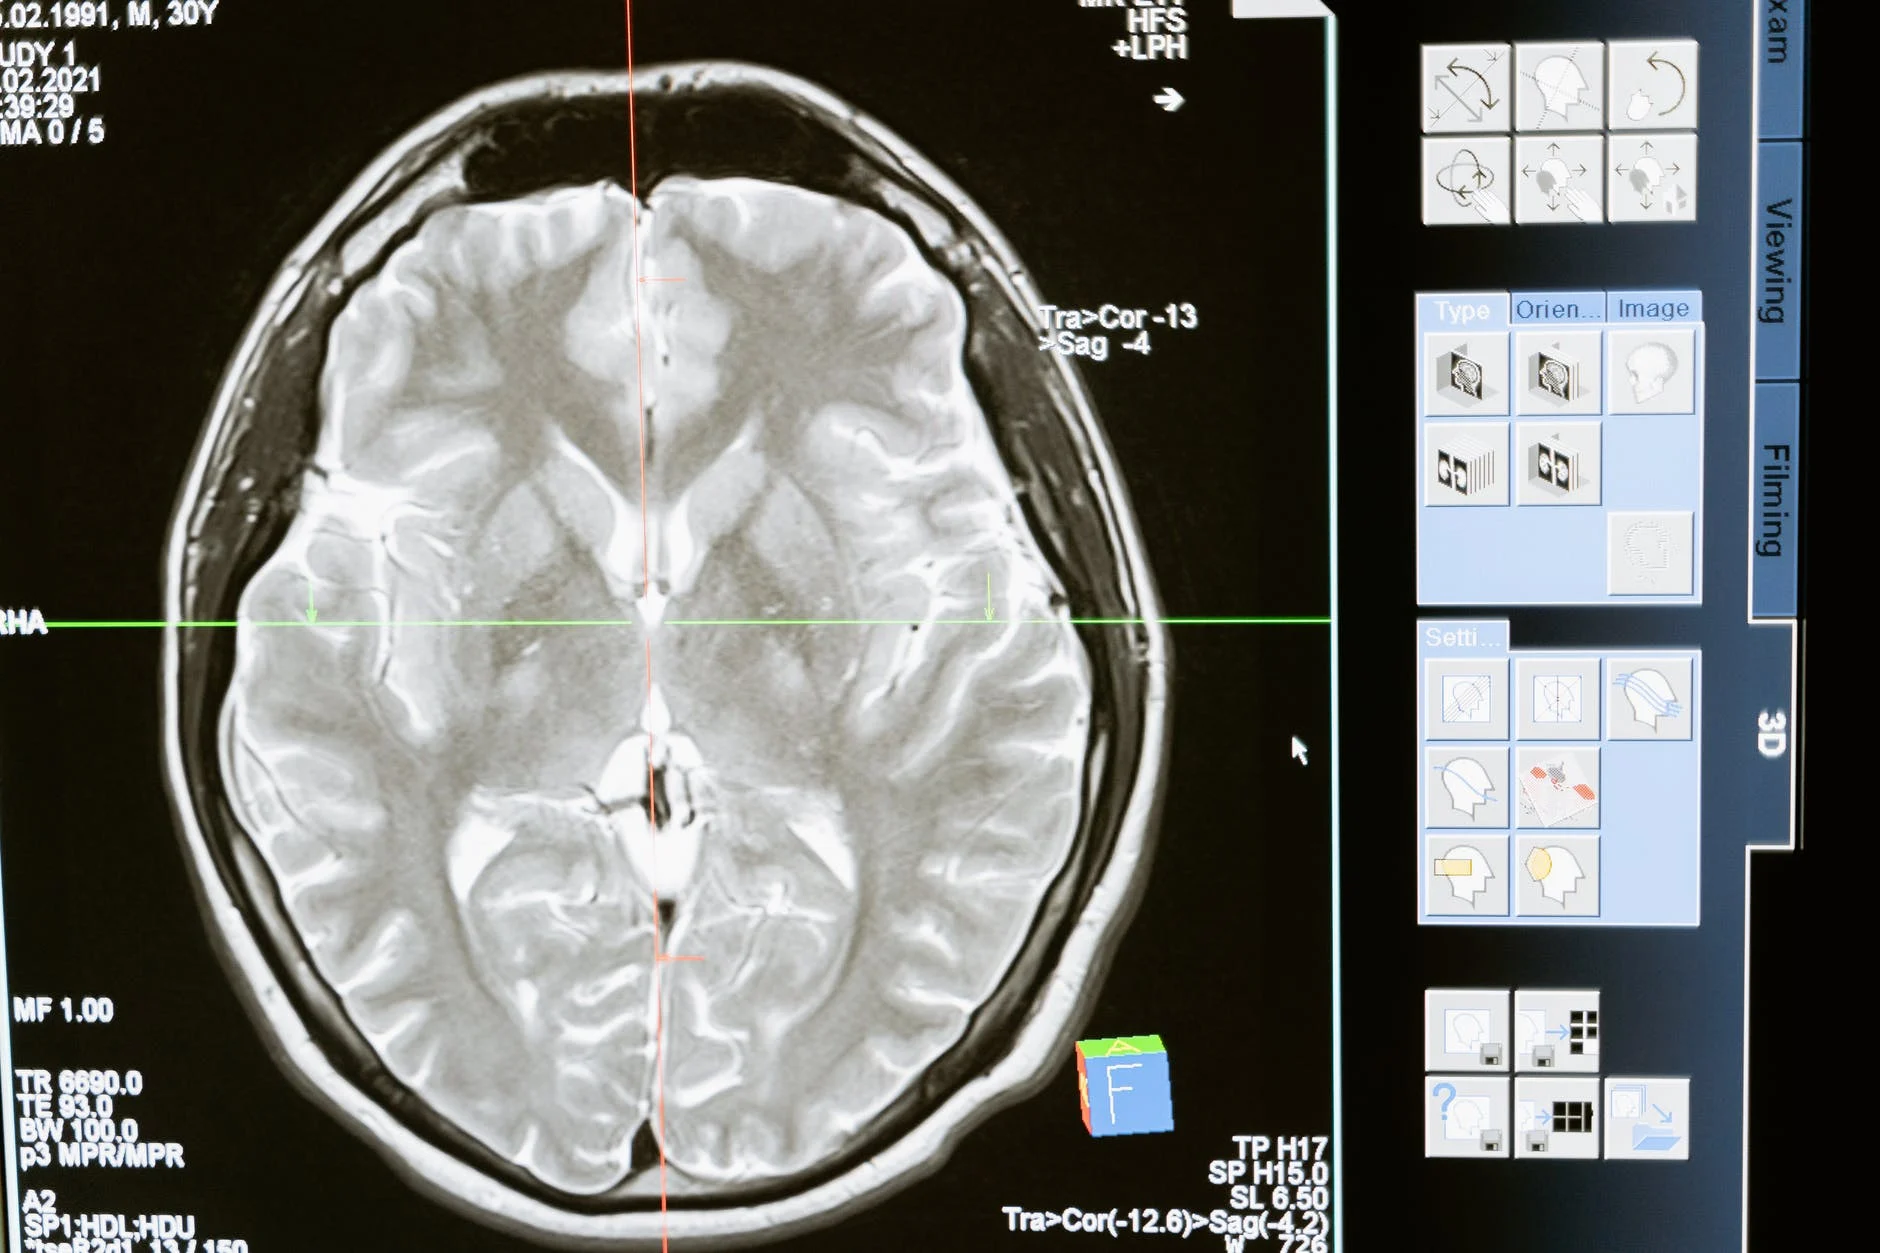

- En el área de medicina, se emplea para realizar contraste en la resonancia magnética nuclear